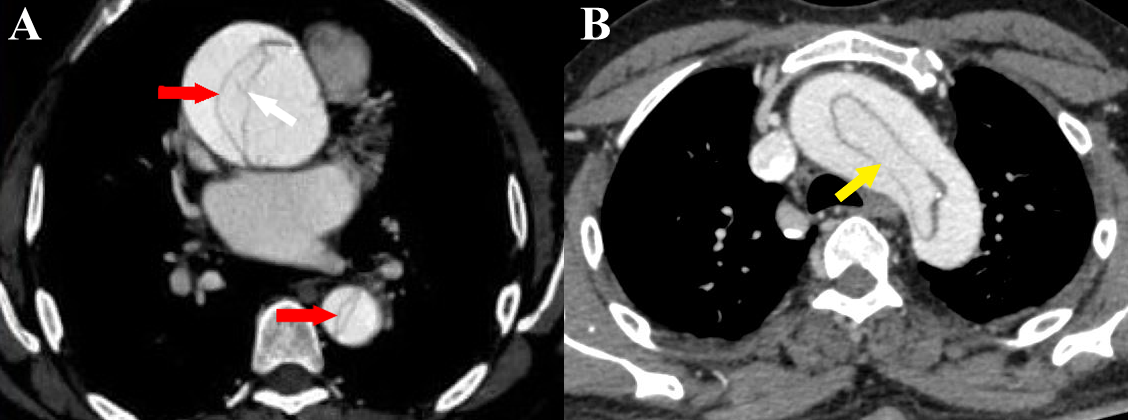

Figure 5 a-b Stanford type A aortic dissection. (a) Axial CT angiography image shows the dissection flap (red arrows) in ascending and descending aorta. Also seen are linear hypodense structures within the false lumen (white arrow) with similar attenuation as the intimal flap (“Cobweb sign”) [courtesy of Dr Suhas C. M, final year resident, MD Radiodiagnosis, Ms Ramaiah Medical College, Bengaluru, India]. (b) Axial CT angiography image shows a circumferential flap with oval morphology (“windsock” sign) involving the aortic arch (yellow arrow).

Figure 6 Axial CT angiography image of Stanford type A aortic dissection shows dissection flaps involving the great vessels. Note the “beak sign” (red arrows).